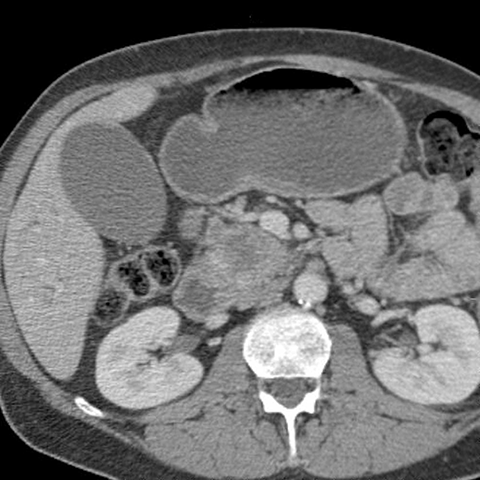

56 year-old male presents with painless jaundice [5 of 7]